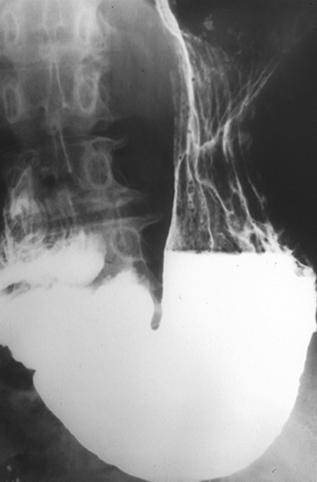

Criteria of Hist.ClassificationMalignant epithelial tumor/Adenocarcinoma

LocationStomach/Body

Technique, MethodX-ray

Macroscopic TypesType 0/IIa (IIa+IIb) Superficial elevated and flat type

Size35 - 40

Depth of Tumor Invasionmucosa